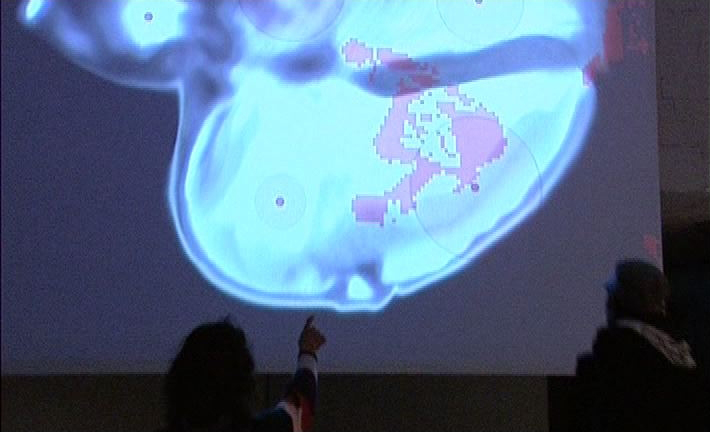

Dentro del espasio expositivo se instaló una superficie de proyecion de 4x5m en la cual se proyecta autentica imagen del corazón de la artista, realizada en cooperación con el equipo médico del hospital y el equipo técnico de rodaje.

El acercamiento del visitante a cierta área del mismo esquema inicia un concreto autentico sonido, que se produce en esa parte del órgano. Al mismo tiempo, la superficie de proyección muestra las figuras pixeladas de los participantes y su movimiento en partes del corazón proyectado. El visitante, como el receptor básico y a la vez el factor de cambio, al moverse dentro de la sección esquemática del corazón provoca cambios visuales y acústicos.